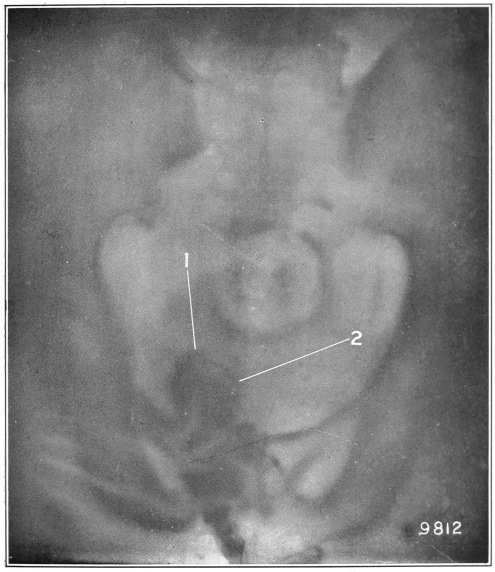

Nine Radiograph Illustrations Showing Mucus Channels and Cavities200

CHAPTER V.

Rebellion of our outraged Internal Economy.

The small intestine is that portion of the alimentary canal which begins at the stomach and ends at the large intestine. Its usual length is twenty feet. The diameter, which at the upper portion (duodenum) is two inches, gradually becomes less, until at the lower end it is but one inch.

Now, the length of the inner coat of this small intestine—the mucous membrane—is about double that of the intestine itself. Think of wearing a coat twice as long as yourself! How do you think this is accomplished in the case of the muscular tube under con­sid­er­ation? Well, Nature, having a most peculiar function to perform, has thrown this mucous coat or tube into a thousand folds (valvulæ conniventes, or “winking valves”). These folds form valves, occupying from one-third to one-half the circum­ference of the bowel. The greatest width of each fold is at the center, where it measures from a quarter to half an inch. Over this great expanse of mucous membrane we find studded ten million five hundred thousand intestinal villi, whose office it is to absorb the food substances in their passage through the canal.

Fig. 9.

Stomach, liver, small intestine, etc. (Flint.) 1, inferior surface of the liver; 2, round ligament of the liver; 3, gall-bladder; 4, superior surface of the right lobe of the liver; 5, diaphragm; 6, lower portion of the œsophagus; 7, stomach; 8, gastro-hepatic omentum; 9, spleen; 10, gastro-splenic omentum; 11, duodenum; 12, 12, small intestine; 13, cæcum; 14, appendix vermiformis; 15, 15, transverse colon; 16, sigmoid flexure of the colon; 17, urinary bladder.

Those that have observed the anatomical illustrations of the small intestines must have been struck by their apparently inextricably tangled convolutions. In life, these convolutions are constantly changing their locations, as though they were a mass of worms.

Fig. 10.

The cæcum, dorso-mesial view, showing the ileum-side of the ileo-cæcal valve, and the beginning of the three muscular ribbons. (Gerrish.)